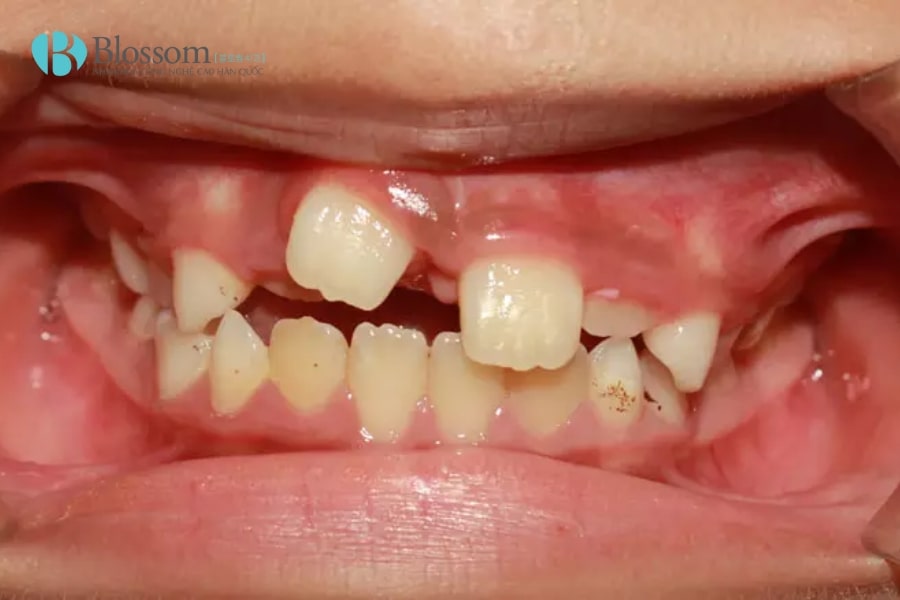

Mọc thừa răng (răng dư, răng kẹ, hyperdontia) là tình trạng có nhiều hơn số răng bình thường và vượt quá 20 răng sữa hoặc 32 răng vĩnh viễn. Răng thừa có thể mọc ở bất kỳ vị trí nào trên cung hàm, phổ biến nhất là vùng răng cửa hàm trên. Chúng thường nhỏ, dị dạng, mọc lệch hoặc ngầm, không có chức năng ăn nhai và có thể ảnh hưởng đến thẩm mỹ, sức khỏe răng miệng.

- Răng mọc lệch, chen chúc, gây khấp khểnh, sai khớp cắn.

2.1. Mọc thừa răng ở hàm trên

Đây là vị trí thường gặp nhất. Răng thừa ở hàm trên có thể mọc ở phía sau răng cửa, giữa hai răng cửa hoặc lệch ra ngoài cung hàm. Một số trường hợp, răng thừa còn mọc ở vùng hàm ếch, gây khó khăn khi phát hiện và vệ sinh răng miệng.